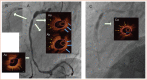

Patients with calcified, fibrotic native coronary vessels with prior suboptimal stenting outcomes are at major risk of stent thrombosis and could face serious consequences if untreated. In cases of multiple layers of under-expanded stents, the risk is multiplied. If conventional balloon post-dilatation is unsuccessful after stent implantation without proper lesion preparation, few interventional options remain. The authors report on a patient with prior numerous right coronary unsuccessful coronary interventions resulting in partially crushed multiple layers of stent material with critical lumen narrowing caused by stent under-expansion. Balloon angioplasty and stent rotational atherectomy (ROTA) had been attempted to overcome stent under-expansion but were unsuccessful. The authors investigated a new combination therapy of laser atherectomy (ELCA) and super high-pressure balloon (OPN non-compliant balloon) to treat single or multiple layers of stent with severe under-expansion due to fibrotic, calcified tissue surrounding the under-expanded stent structure.